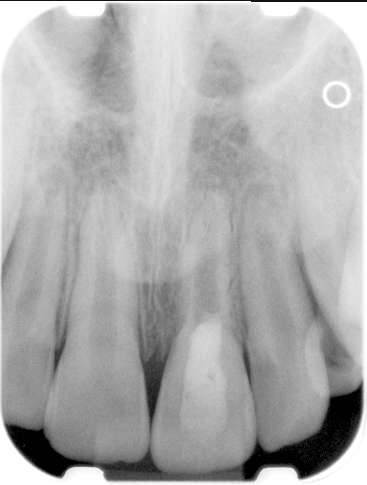

Clinical procedure: If apical bone loss is present (Figure 1) a collagen/gelatin sponge (eg, Gelfoam®, Pfizer Inc., www.pfizer.com) can be placed apically so that the MTA can be delivered to the desired working length. (Any other surgical resorbable sponge would also work, such as OraPlug® [Salvin Dental Specialties, www.salvin.com], Surgifoam® [Midwest Dental, www.mwdental.com], or Surgispon® [Aegis Lifesciences, www.surgispon.com]). This is done by taking a small piece (2 mm x 2 mm) of the resorbable sponge and pushing it down to and through the root apex with an endodontic file. Once this is done, MTA is packed down the canal with a custom-fitted cone. The clinician can use a rubber stopper on the gutta-percha cone to know the exact length of MTA placed in the apical third (Figure 2). Once the apical third is sealed with 3 mm to 5 mm of MTA, the remaining coronal canal space can be back-filled using a warm gutta-percha technique (Figure 3).

Fig 1. Preoperative radiograph showing apical bone loss.

Figure 1

Fig 2. MTA placed in the apical third.

Figure 2

Fig 3. Postoperative radiograph.

Figure 3